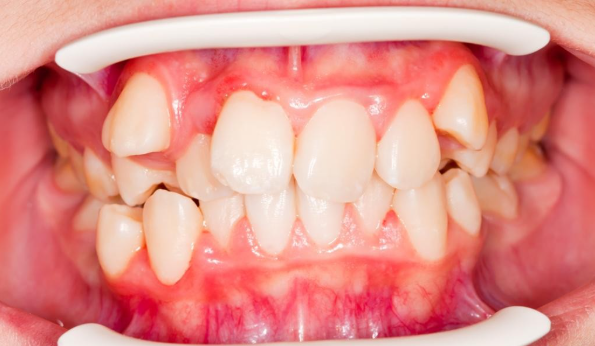

- 덧니(총생, Crowding)

환자분이 흔히 생각하시는 부정교합입니다.

치아가 삐뚤빼뚤한 상태죠~~

겹쳐지기도 하고 치아 배열이 안좋다보니

칫솔질이 어려워 충치나 잇몸 질환이 발생할 확률이 높아요~